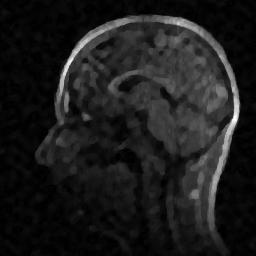

6.3. MR Image reconstruction

The second imaging application is concerned with medical imaging. Following the ideas from [32, 34], we simulate a multi-channel MRI sensing set-up, first using the same sine waves as in the previous experiment (results displayed in Fig 10), and then using spherical beam pattern (see in Fig. 11 for the results). We generate the classical Shep-Logan phantom, and set its dimension to .

The first experiment, depicted in Fig. 10 shows the results obtained by our method when using a Daubechies 4 sparsifying dictionary. Our results are compared to the single sensor analysis, and the results obtained by the Sum-of-Squares recovery [34, 32].

The recovery is obtained from noisy measurements, in which some additive Gaussian noise with variance has been added. The measurements are obtained by subsampling ( samples) of the Fourier transform. We see here that the fused compressed sensing is better capable of handling a multi-channel problem with unusual illumination (compared to the Sum-of-Squares method). Moreover, more details are preserved, when compared to the single sensor analysis method.

Some noise still appears in the image, but can easily be thresholded further if needed. One important aspect of MR Images that hasn’t been considered in this research, is the fact that they are sparse in gradient. One usually prefers to minimize the Total Variation instead of the norm or another frame using analysis.

Although we have not explicitly written the theory here, the recovered images in Fig. 11 show the results when using a TV minimization instead of the analysis.

The results were obtained from a spherical beam illuminating the input image. The measurements are obtained by sampling ( samples) of the Fourier coefficients at random iid from a Gaussian distribution. Again, some Gaussian noise with variance is added to every measurements.

As presented in these examples, our method is capable of handling highly complex signals in potentially many dimensions yet keeping a very low number of samples taken. We can also empirically verify that the presented approach enjoys more robustness to noise and variations in scene illuminations than other known methods.

This behavior is true for both images, which are real-world images of brain scans. It is worth keeping in mind that SSIM is a structural similarity which tries to emulate the human visual perception while the other metrics are pure machinery. As can be seen both from the figures and the tables, the proposed method performs at least as well as previous approaches, and may behave better when considering total variation minimization.